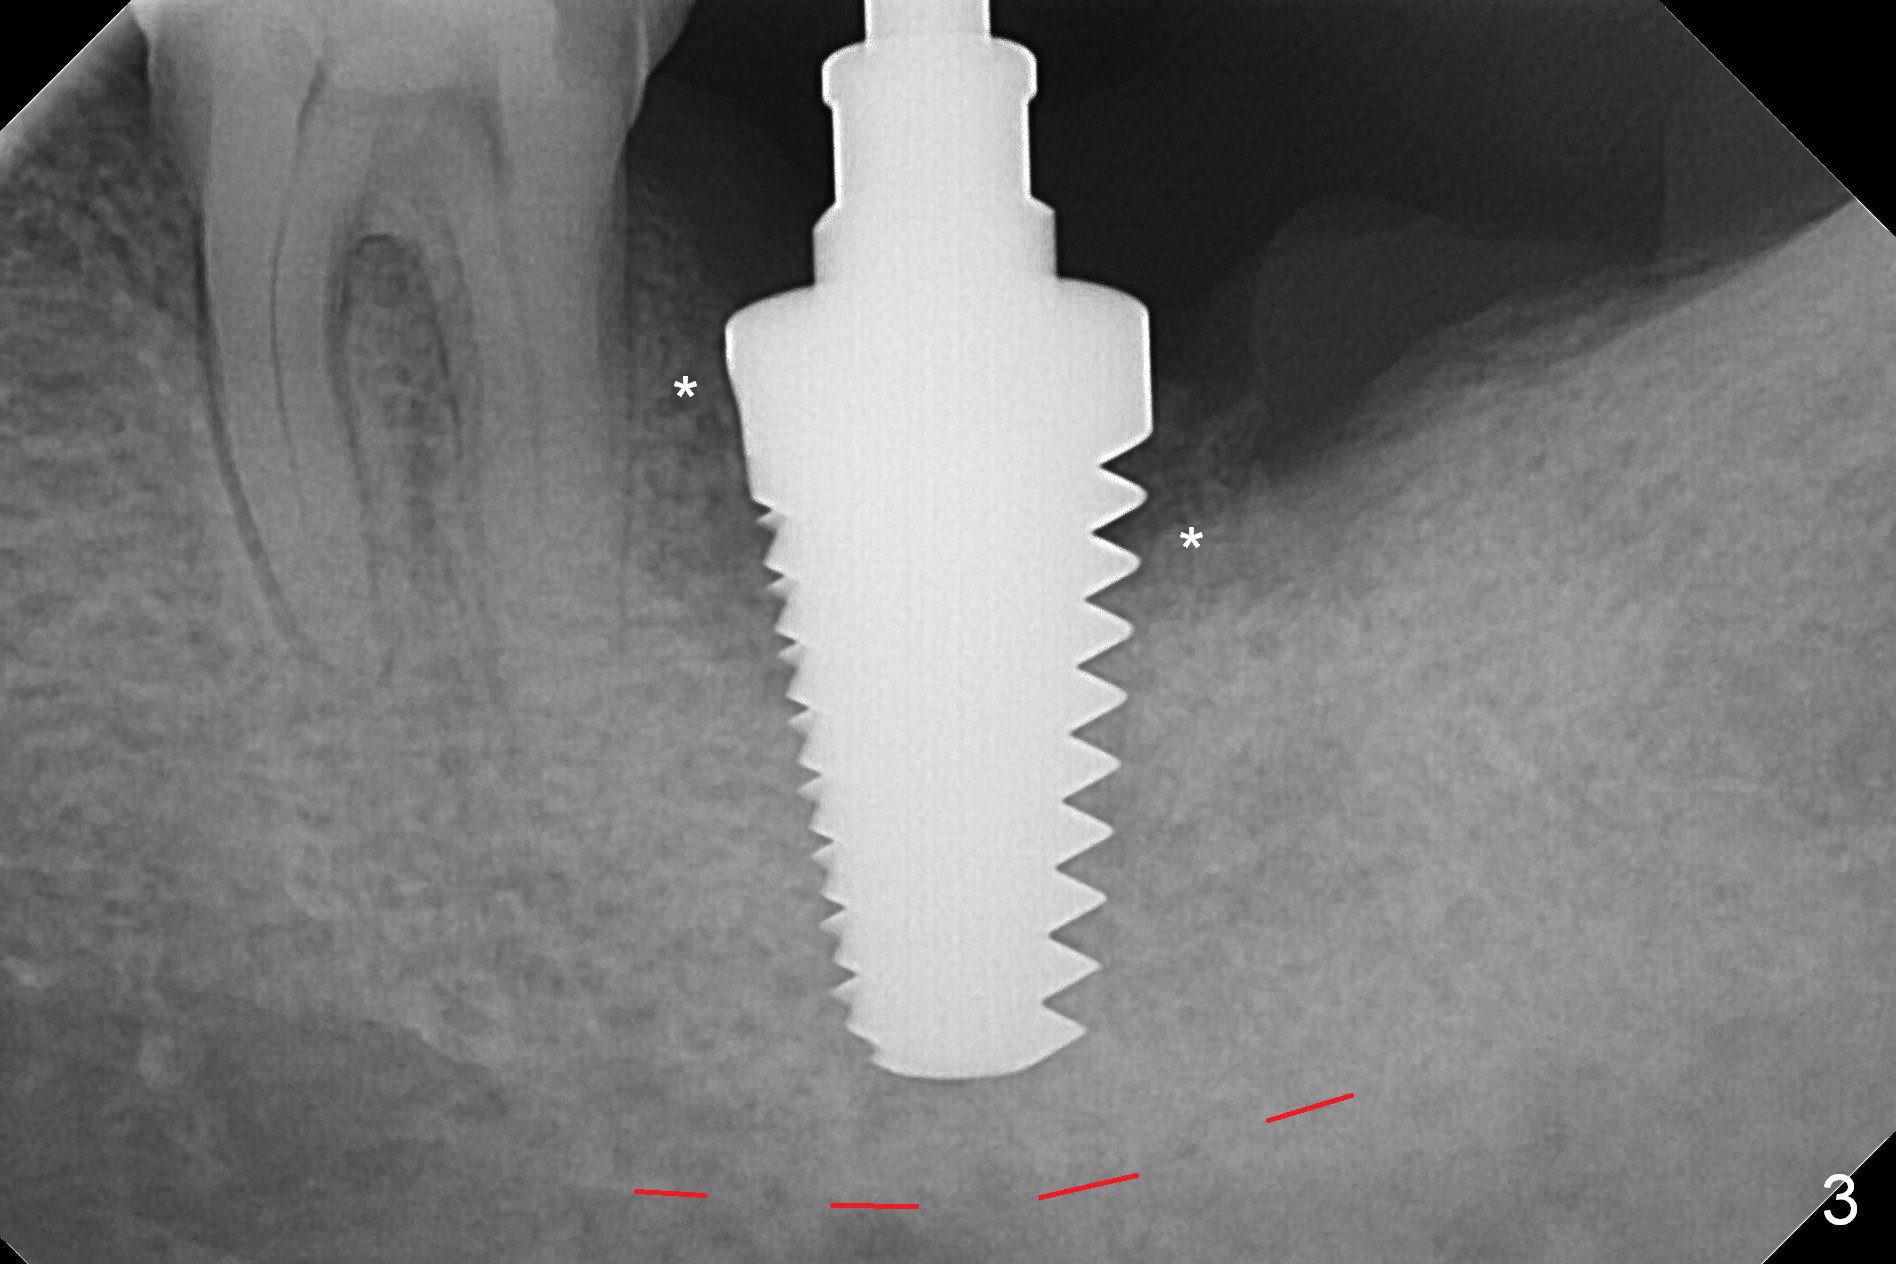

When the tooth #18 is extracted, the buccal and lingual plate are absent. Initial osteotomy is established in the middle of the socket (Fig.1). After 4.3 mm Magic Drill (15 mm from the buccal gingival margin, new bone ~ 4 mm), a 5x9 mm IBS dummy implant is placed with correct trajectory (Fig.2). Since the bone density is seemingly high, the same size of a definitive implant is placed with primary stability. The trajectory is found not ideal after bone graft and insertion of an abutment (data not shown). The stability is lost when the trajectory is changed. No primary stability is achieved with a larger (5.5x9 mm) implant. Tatum tapered taps (6x17, 7x17 and 8x17 mm) are used. The latter obtains stability with contact with the mesial and distal crests (Fig.3 *). A 8x14 mm tissue-level implant is placed with insertion torque ~ 55 Ncm (Fig.4). A 6x3 mm abutment (Fig.4 A) is placed to retain an immediate provisional (Fig.5 P). The drawback of the extra large implant is lack of bone buccolingually. Oral hygiene is emphasized so that the buccal and lingual bone have chance to regenerate. Fortunately there appears to be no paresthesia postop.